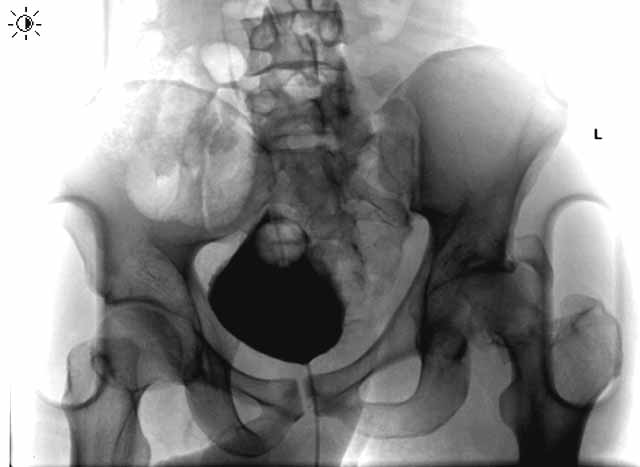

Here are some interesting plain films and CT images for a 22 yo male involved in an auto accident who was then struck as a pedestrian when he exited the vehicle.

AP Pelvis

He has a left sided sacroiliac injury with an associated posterior iliac fracture, femoral head fracture, femoral neck fracture with extruded head-neck fragment, and posterior wall acetabular fracture with osteochondral impaction.